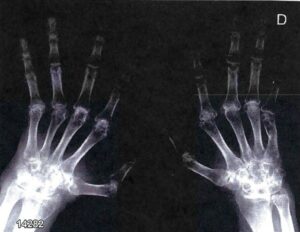

Tra le complicanze vi sono anche la febbre reumatica (coinvolgimento cuore, articolazioni, sistema nervoso, cute) e la glomerulonefrite post-streptococcica (patogenesi non legata alla presenza del batterio ma a fenomeni immunologici per la presenza della proteina M dello streptococco con epitopi molto simili a quelli della sinovia e delle valvole cardiache). Oggi queste due complicanze sono piuttosto rare per via dell’utilizzo di antibiotici che trattano l’infezione.